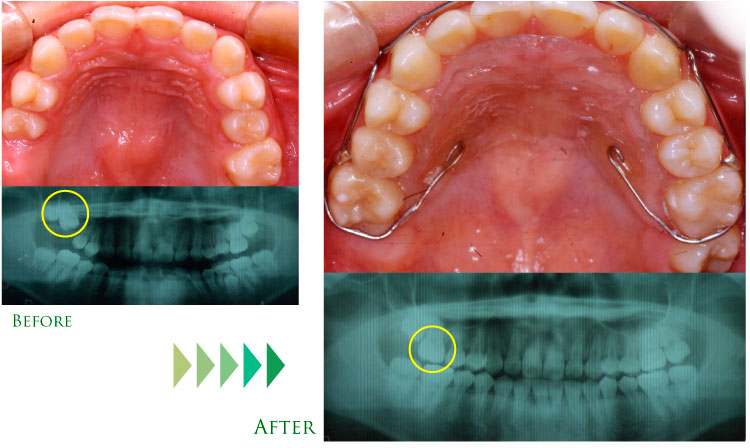

●埋伏歯の有効利用